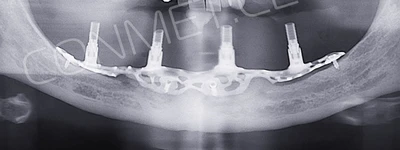

1. Пациенту было произведено МСКТ исследование нижней челюсти, с последующим созданием STL модели. В зуботехнической лаборатории был изготовлен восковой шаблон с искусственными зубами с учетом индивидуальных прикусных взаимоотношений (пока это делает зубной техник точно так же, как при изготовлении съемного пластиночного протеза).

2. После этого произвели компьютерное моделирование самого имплантата и фиксирующих элементов. Примечательно, что в абатментах, использовался отлично зарекомендовавший себя и проверенный десятилетиями интерфейс КОНМЕТ! В результате получили несколько специальных файлов, позволяющих не только сделать сам имлантат, но еще до операции изготовить и сами зубы. Данные файлы передали в изготовление на специальном 3D оборудовании.

Имплантат напечатали из особого, биосовместимого, медицинского титана на предприятии имеющим соответствующую медицинскую лицензию. Толщина имплантата составила 0,8 мм, а вес всего несколько грамм!